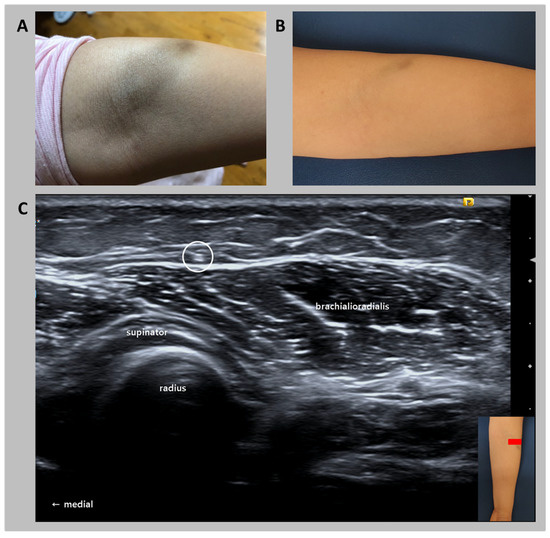

Compression of the Lateral Antebrachial Cutaneous Nerve due to Leakage of Iron after an Intravenous Iron Infusion